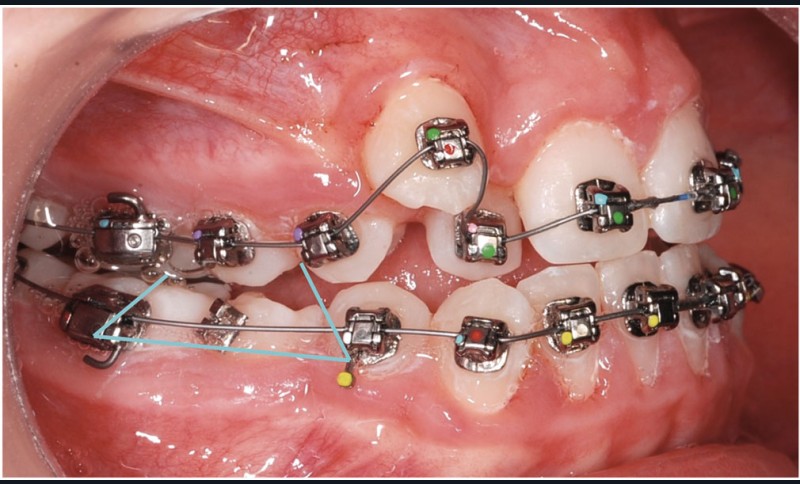

Le cas d’Anthony âgé de 11 ans et 7 mois qui présente une endomaxillie bilatérale associée à un léger encombrement mandibulaire dans un contexte de classe I squelettique hyperdivergente (fig. 1 à 10) est très représentatif de ce que peuvent apporter les forces légères appliquées aux alvéoles dentaires tout en intégrant des torques spécifiques qui permettent de contrôler parfaitement l’orientation radiculaire (fig. 11 à 29).

Le système laisse beaucoup de liberté dans l’interface entre bracket et arc : la vascularisation, et donc le recrutement cellulaire et la reconstruction osseuse s’en trouvent améliorés, la mise en place de l’occlusion se fait sous le contrôle de la matrice fonctionnelle, car les forces engagées restent en dessous de la puissance des forces masticatrices notamment.